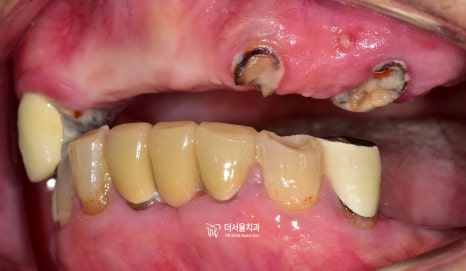

더서울치과에 오셨던 이 분의 경우,

구강 내 온전한 치아가 거의

없는 상태로 오셨었습니다.

이미, 치아의 결손 범위가 넓으셨으며

남아있는 치아들도 치근만

남아있는 곳이 거의 대다수입니다.

과거 부분 틀니를 오래 써오셨으며,

유지력을 얻게 도와줬던 surveyed crown 이

있던 위치는 치근만 남아있네요.